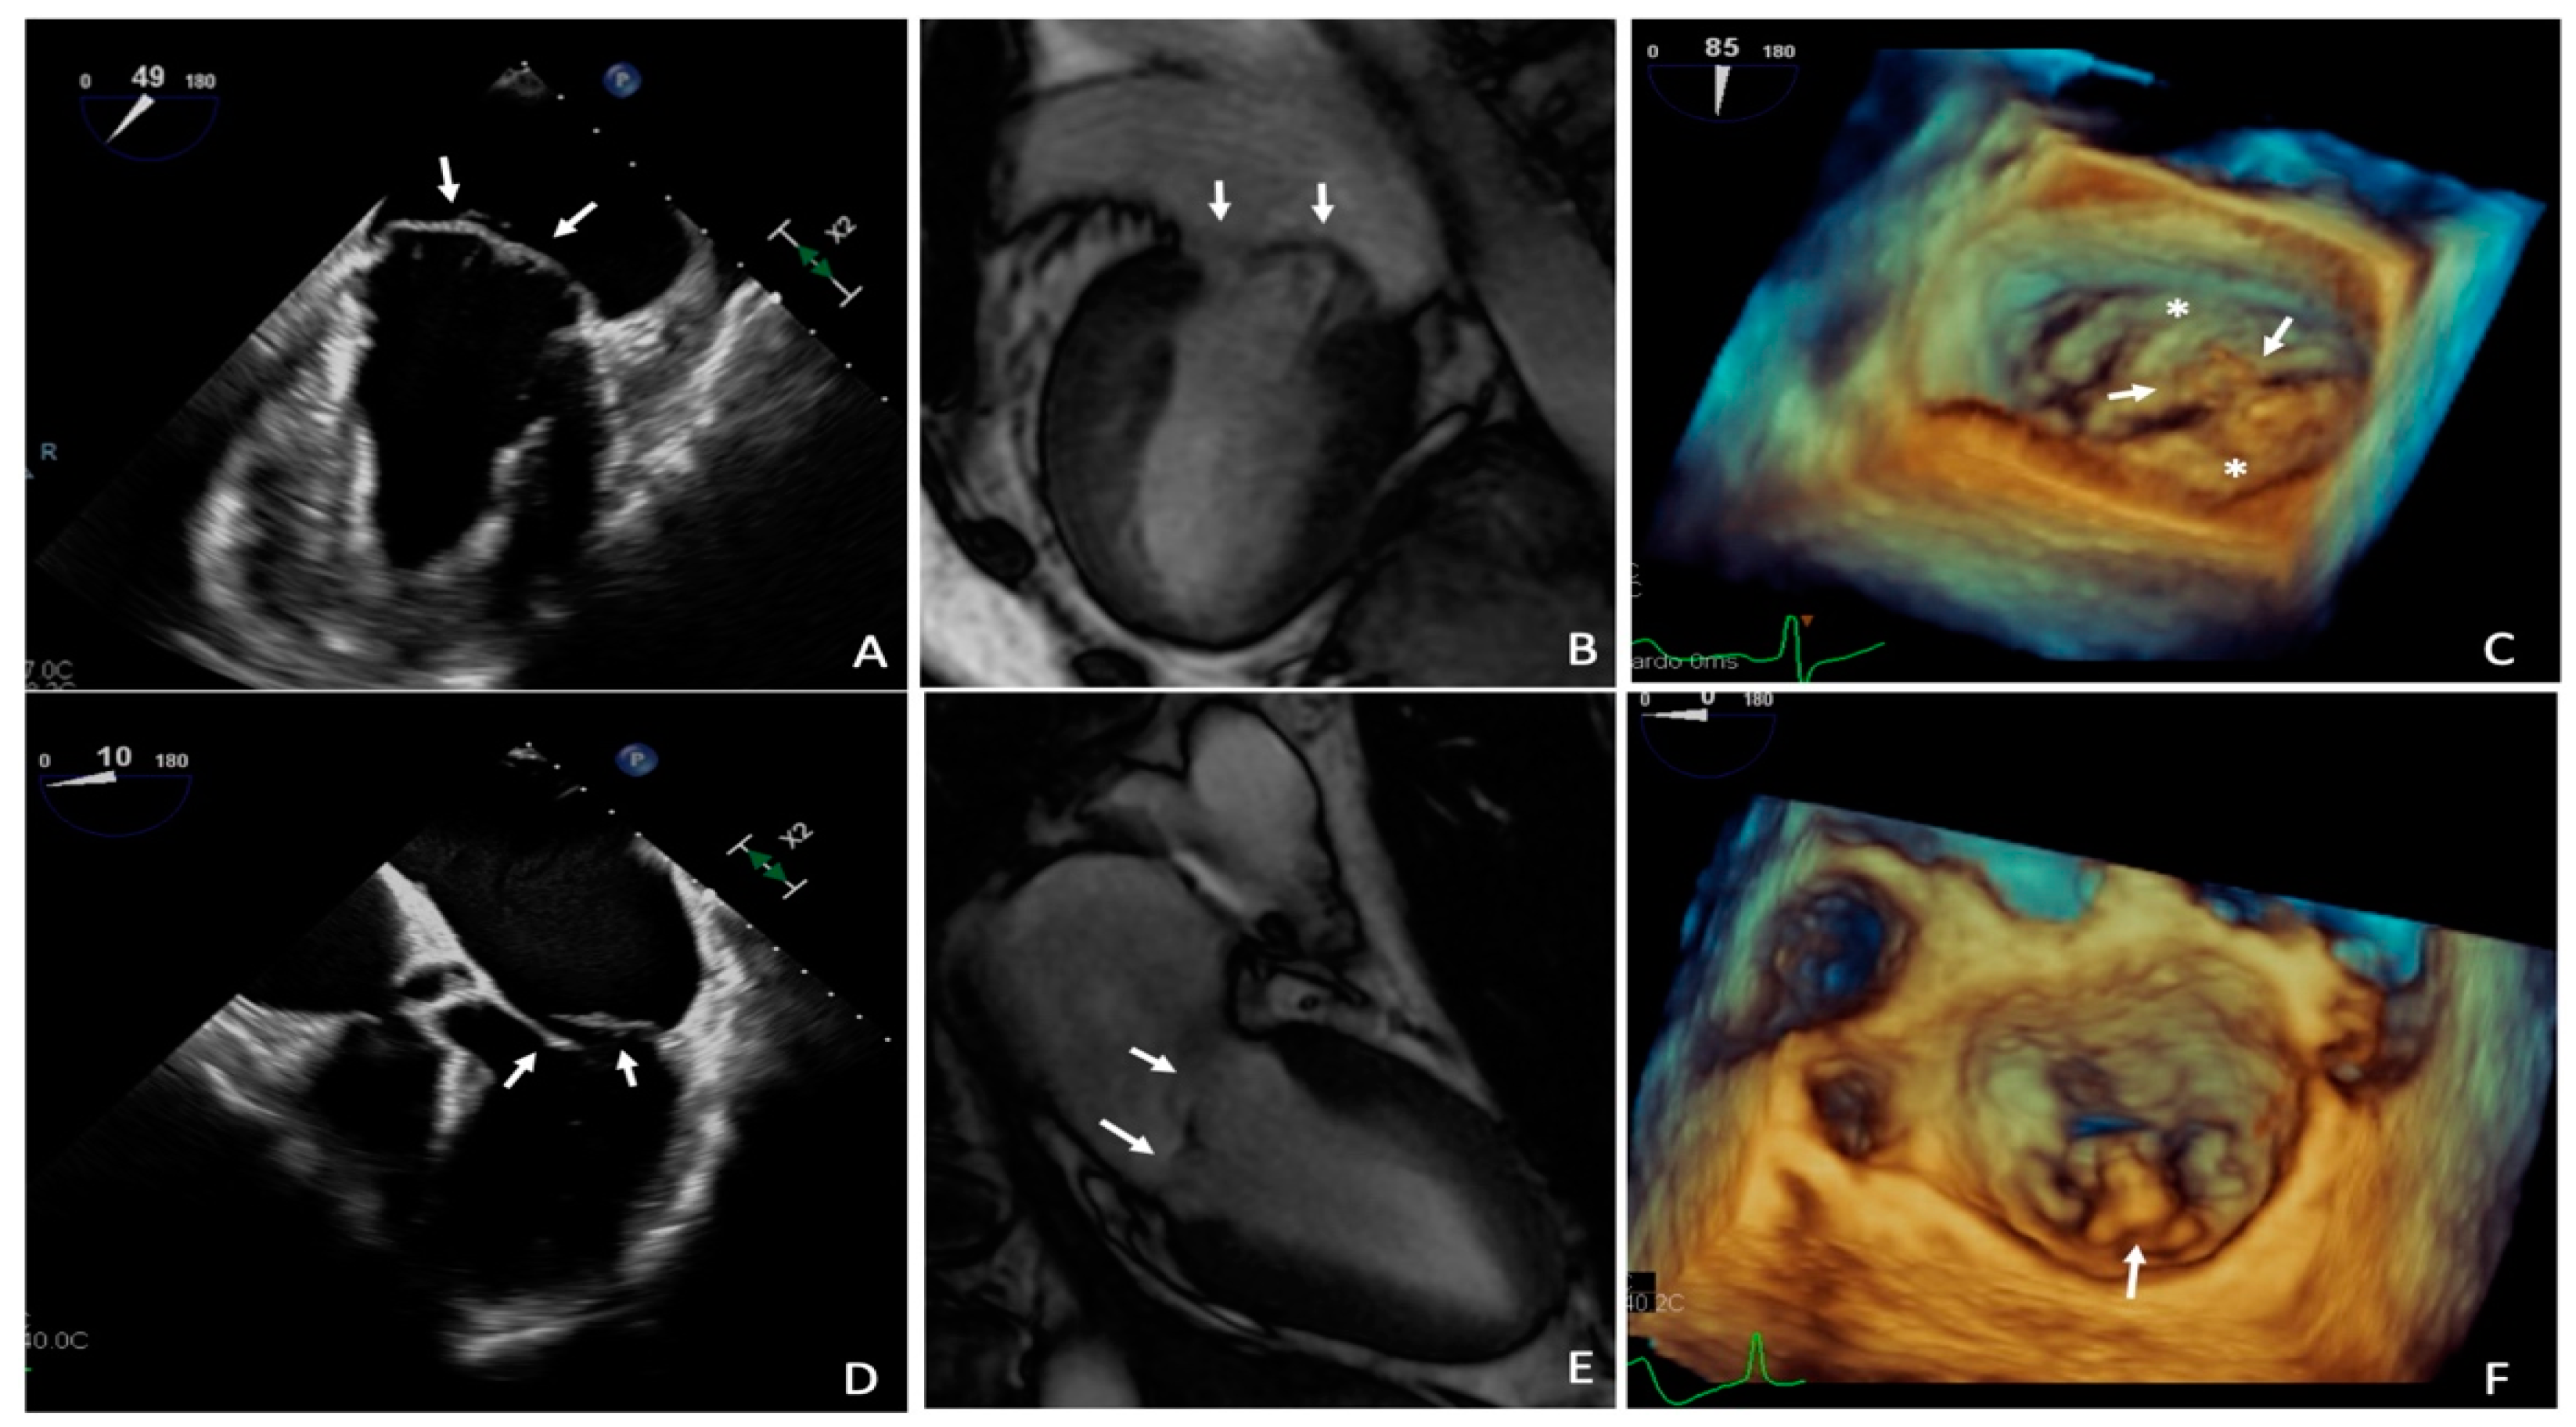

4.1. Mitral Valve Leaflet Alterations

4.2. Mitral Valve Annulus Alterations

4.3. Myocardial Structural Abnormalities